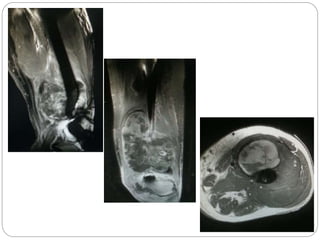

This document discusses 8 oncology cases. Case 1 involves a 40-year old female with right knee pain. Case 2 is a 28-year old male with a left subtrochantric fracture from a MVA who is now experiencing increasing left knee pain and swelling. Biopsy results showed high-grade osteosarcoma. Case 3 is a 30-year old female with breast cancer and bone metastases causing bilateral hip pain.